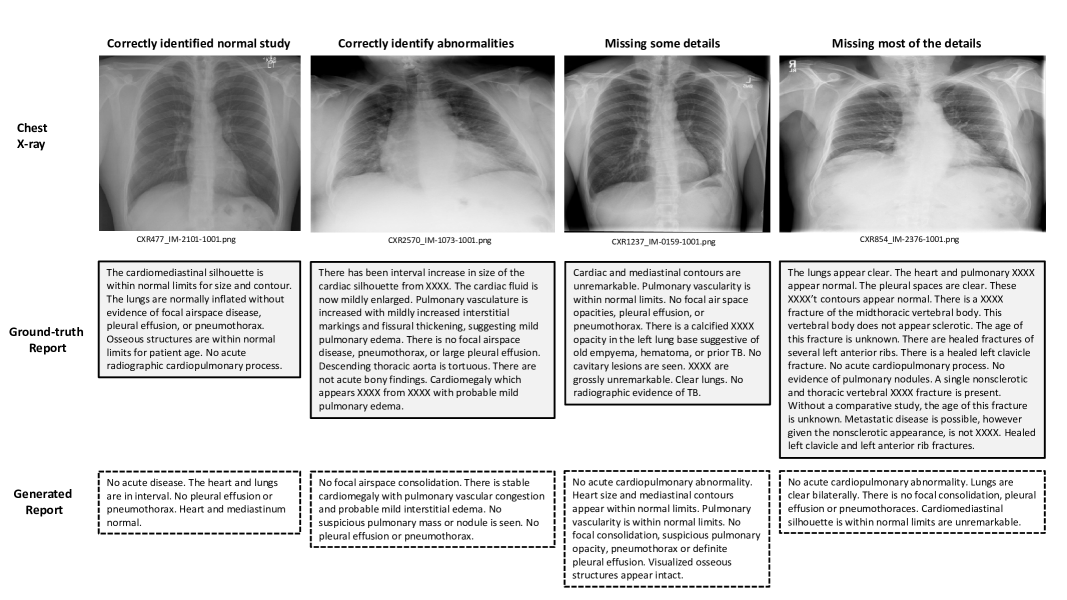

Refer to caption

Figure 6: Selected sample cases for radiology report generation with increasing difficulty. Bold words represent statements that produce the same meaning as in the ground-truth report.

Figure 6 highlight four selected cases for radiology report generation. The first case shows the model’s ability to correctly identify a normal study by highlighting salient normal regions in the chest X-ray. Given that the number of normal studies outnumber the abnormal studies in most medical imaging datasets, the first case is an easy problem when the language model can easily learn from majority of the text data. In the second case, model can correctly identify abnormalities such as cardiomegaly, pulmonary vascular congestion, and interstitial edema. However, the model is unable to generate sentences such as “there has been interval increase in size of cardiac silhouette from XXXX”. Based on our analysis, we find that radiologists have previous studies for comparison and this is a similar case, where radiologist compare current study with the previous one having date XXXX. Because of not utilising background information for radiology report generation, our model is unable to generated such sentences. We also find that certain words such as stable are temporal in nature. Most of the studies, including our current study, do not have access to longitudinal data, it is hard to apply temporal learning in radiology report generation methods. In the third case, the model is able to correctly highlight normal regions, but misses key findings of calcified XXXX opacity. We find this is due to the lack of context for the need of current radiographic study. In the indication section, physician writes why the particular radiology study is asked for. This background context can guide radiologists to look specifically to answer the clinical question. On checking the indication section in the ground-truth report of the third case, we find sentence “XXXX-year-old male with positive PPD”, which clearly indicates that radiologist is investigating whether radiology study shows any symptoms of tuberculosis (TB). This is evident from the sentence “No radiographic evidence of active TB” in the ground-truth report. The fourth example highlights one of the challenging case, given the nature of the study and usage of words in the report. Given cases related to fractures are rare in the dataset, it is challenging for language model to learn and generate such sort of examples.